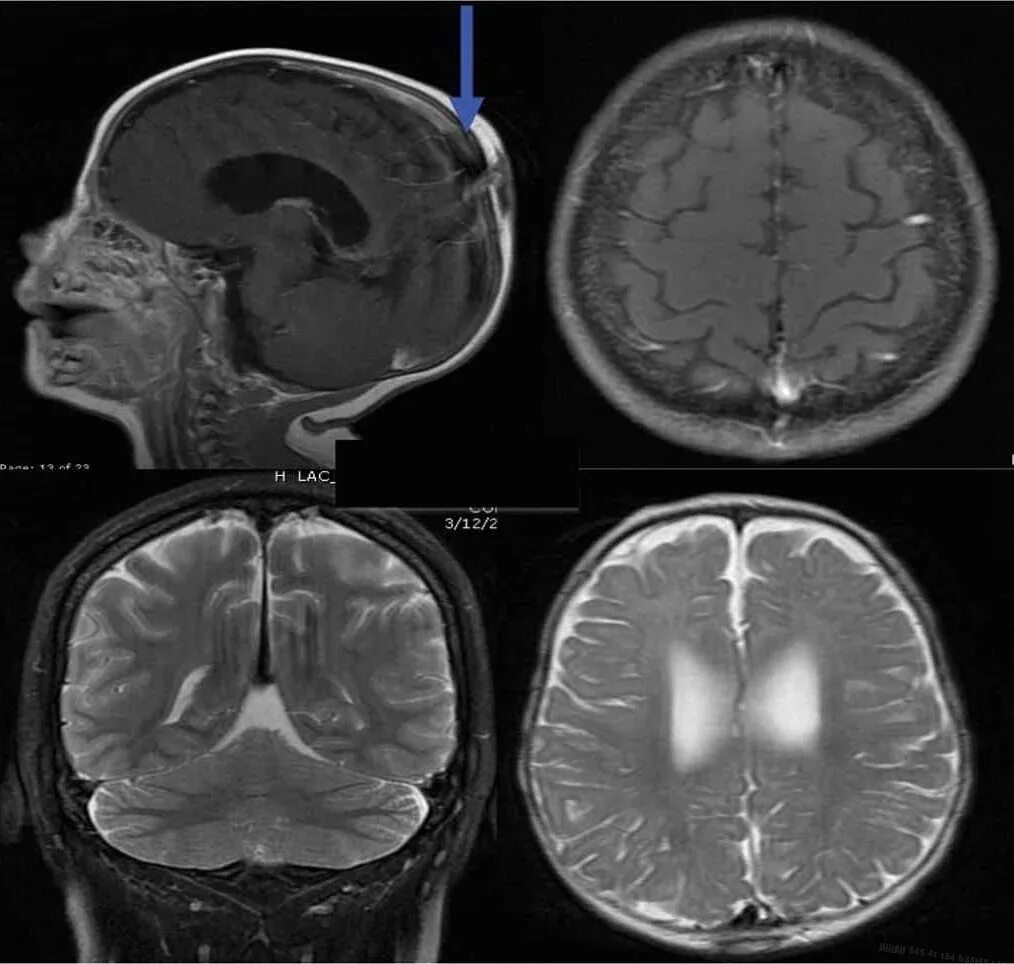

Что покажет мрт головного мозга с контрастом